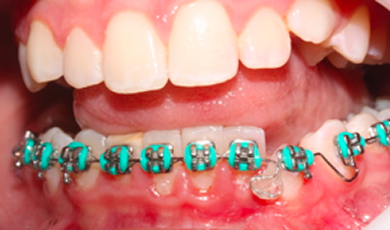

Evolução do tratamento ortodôntico

Evolucao do tratamento ortodontico ja com a instalacao do apararelho fixo em alguns dentes auxiliando o tracionamento do dente incluso.

Evolucao do tratamento ortodontico com o apararelho fixo colado em todos os dentes inferiores e o elemento 33 ja melhor psicionado.